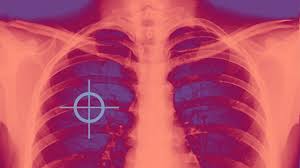

Learn more about common lung cancer symptoms. Most lung cancers do not cause any symptoms until they have spread, but some people with early lung cancer do have symptoms. A persistent cough could be a symptom of lung cancer or head and neck cancer. What are the symptoms of lung cancer? Identifying lung cancer symptoms can save lives! Diagnosing the lung cancer at an early stage would be helpful in the better treatment and. When lung cancer does cause signs in its early stages, they may vary from person to person but commonly include The symptoms of lung cancer range, like a chronic cough, can be easy to ignore or dismiss, but doing so can delay vital treatment. We are going to study the in and out of lung cancer symptoms today. 1 cause of lung cancer, according to the american lung association. Before we actually jump on to our main topic of signs and symptoms of lung cancer, we would like to share some important facts related to lung cancer. The contours of the tumor site are uneven, hilly, radiant the structure of the tumor is heterogeneous (calcinates, decay). Symptoms of lung cancer can include a persistent cough, shortness of breath, coughing up blood, arm or chest pain, and unexplained weight loss.

Bob Dole Lung Cancer Learn The Symptoms And Causes from media-cldnry.s-nbcnews.com Symptoms of escherichia coli become an expanded clinical picture of intestinal dysbiosis: They are most effective in cancers with specific changes in their genes or cell receptors. Symptoms of lung cancer can include a persistent cough, shortness of breath, coughing up blood, arm or chest pain, and unexplained weight loss. Lung cancer usually has no symptoms in its early stages. Many of the signs and symptoms can also be caused by other medical conditions but finding lung cancer early can mean that it's easier to treat. Some common symptoms of lung cancer include, according to lungcancer.com Signs and symptoms of lung cancer are not always present until the disease advances. So if you notice any symptoms or changes get them checked out by your gp as soon as.